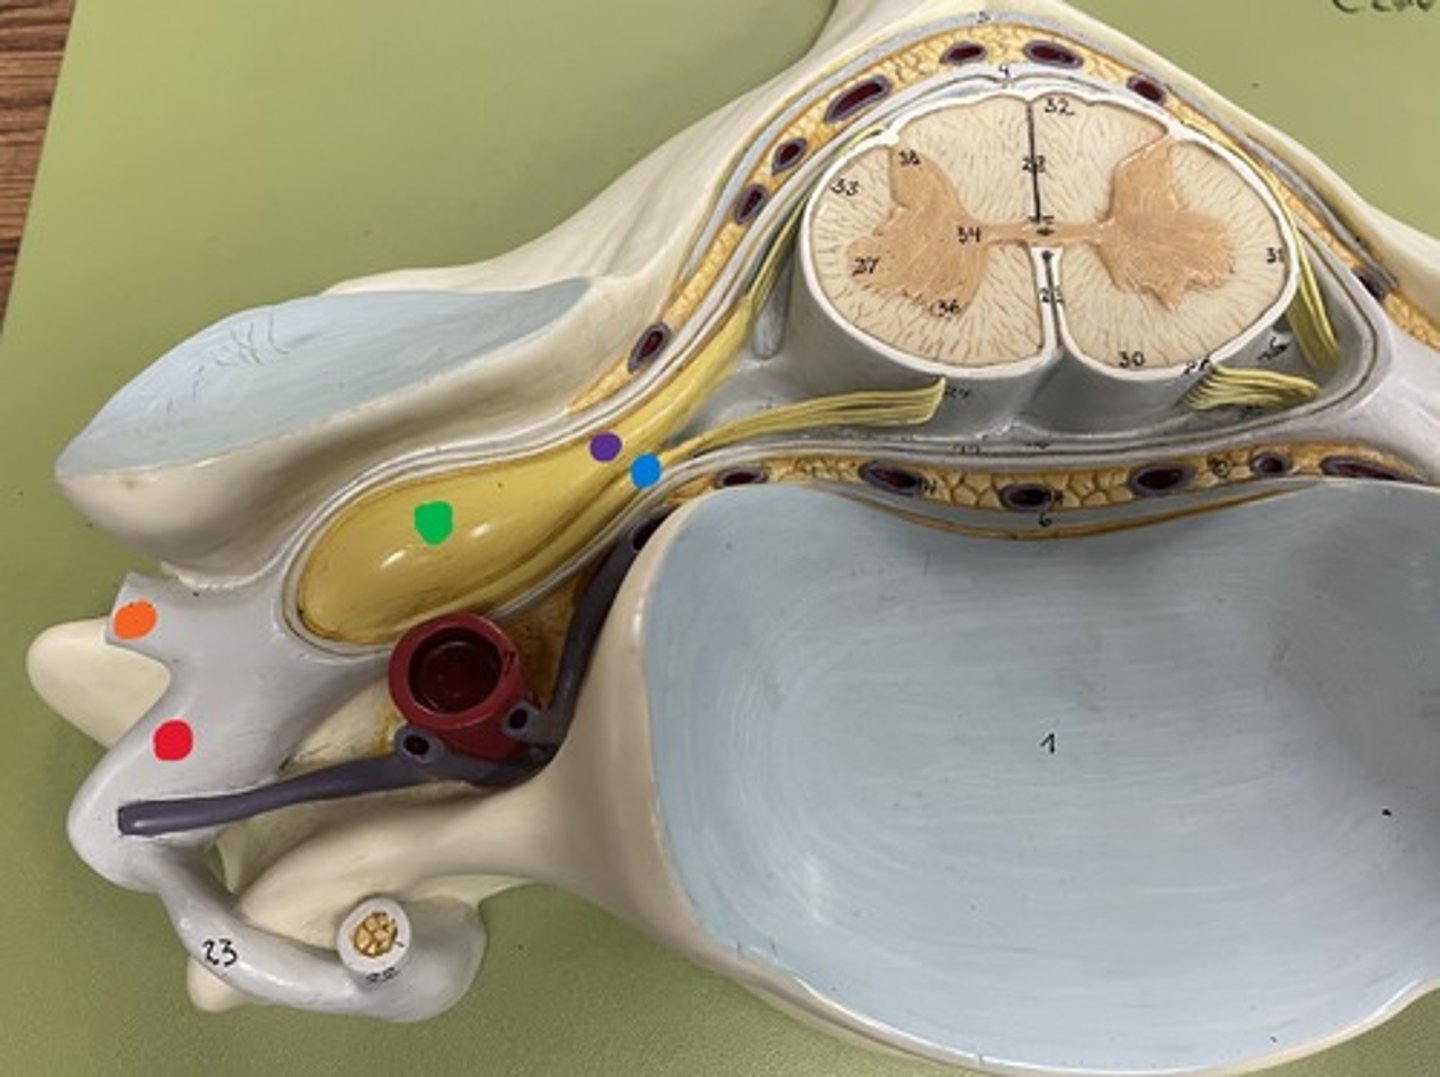

Cauda equina

Red

Filum terminale

blue

Posterior root

purple

Posterior root ganglion

green

Posterior ramus

orange

Anterior root

blue

Anterior ramus

red